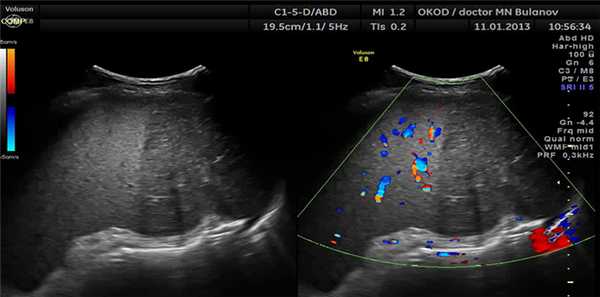

В настоящее время при широком внедрении неинвазивных диагностических методов очаговые образования селезёнки нередко выявляются случайно при ультразвуковом или КТ (ЯМРТ) исследованиях во время профилактического осмотра.

В последние годы широкое распространение получила спиральная компьютерная томография (СКТ) с внутривенным болюсным контрастным усилением при использовании неионных контрастных препаратов (ультравист, визипак, омнипак). Сначала выполняется бесконтрастное сканирование брюшной полости, а затем – исследование СКТ с БКУ (внутривенное введение 100 мл контрастного вещества со скоростью 3 мл/сек) с различными временными задержками сканирования (от 17 до 40-80 сек.).

Использование данной методики позволяет четко разграничить неизменные тканевые зоны, которые хорошо накапливают контрастный препарат, от участков тканевого распада и жидкостных скоплений. Кроме того, удается получить более полное представление об ангиоархитектонике самой селезенки и прилежащих магистральных сосудов, что во многом способствует высокой дифференциальной диагностике между кистами и опухолевыми поражениями. Диагноз СКТ, как правило, подтверждается морфологически в 95% наблюдений.

Таким образом, желательно в современную предоперационную диагностическую программу включать УЗИ, дуплексное сканирование, КТ и МРТ, причем именно в такой последовательности, так как каждый метод, дополняя предыдущий, решает более узкие, конкретные задачи. Конечно, ни один из них не является абсолютным при выявлении очаговых поражений селезенки.

Обращает на себя внимание частота диагностических ошибок при выявлении образований селезенки, которая достигает 75-80% даже при использовании современных методов исследований. Поэтому здесь необходим комплексный подход с использованием всех современных диагностических методов.